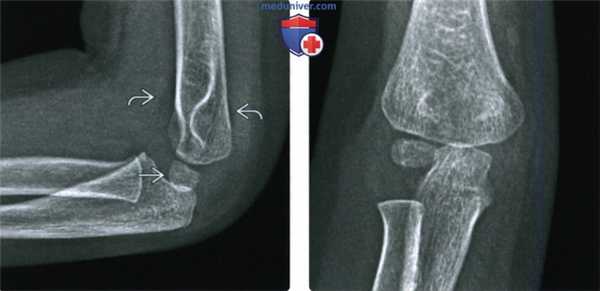

(Слева) На боковой рентгенограмме у четырехлетнего мальчика определяется надмыщелковый перелом плечевой кости после падения на выпрямленную руку. Обратите внимание на смещение головки кзади относительно линии вдоль переднего коркового слоя дистального эпиметафиза плечевой кости. Положительный симптом жировой подушки подтверждает внутрисуставную природу перелома. Следовательно, это действительно чрезмыщелковый перелом.

(Справа) На передне-задней рентгенограмме у этого же пациента не видна линия перелома, что является характерным для этой возрастной группы, кроме случаев с переломом с более значительным смещением.